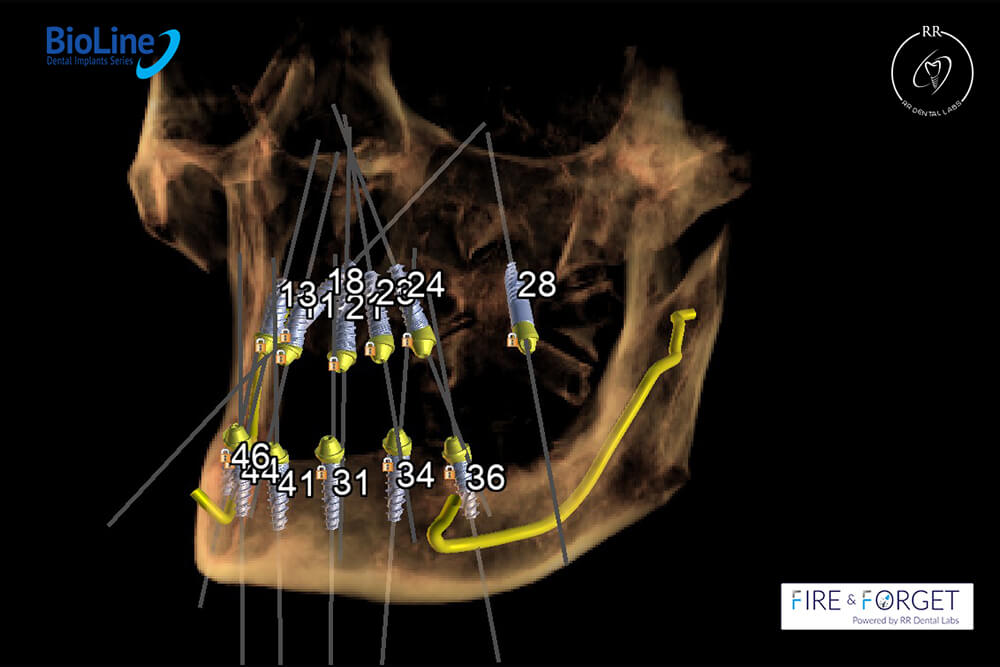

Case 47